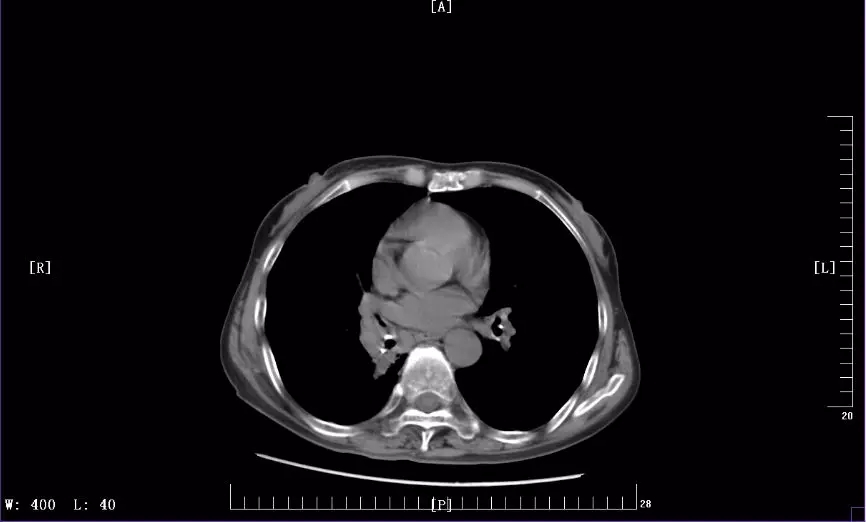

下图是徐丽参加KEYNOTE-407临床试验前后CT影像对比图:

2018年12月最近一次治疗后CT影像